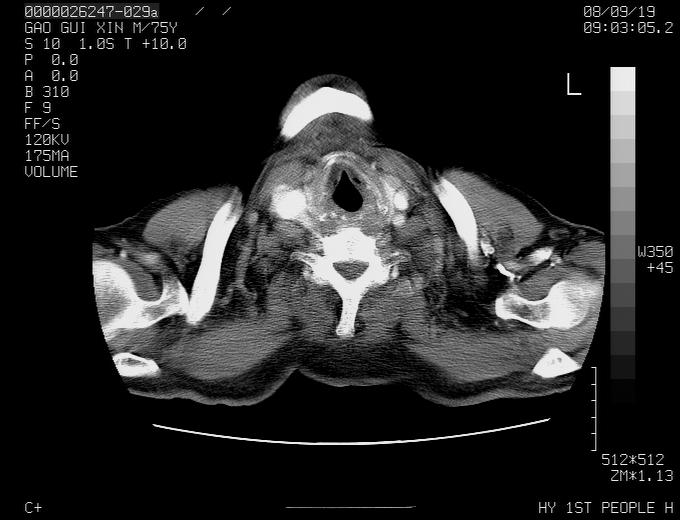

感谢各位老师的意见,左上肺病灶,我本人趋向结核,原因:左上肺见两个类圆形结节,仔细回顾4月份ct似乎原片在该处有条片状密度增高影,强化不明显。

现上传增强片,请各位老师仔细帮我看一下。

右上肺可见条索状影,并可见钙化,左上肺结节可以考虑为结核球,但气管前腔静脉后有肿大淋巴结,本人觉得左上肺结节不能排除转移瘤的可能,右上肺为陈旧性结核灶。

左肺上叶周围性肺癌并纵隔多组lnm.不可能是tb.

左肺上叶尖段瘢痕癌并纵隔淋巴结转移解释更好一些.

双上肺继发型肺结核,纵隔淋巴结结核可能性大,建议定期复查.

左肺周围癌并纵隔淋巴结转移,另一小结节是血管影

别再ct讨论了,一个纤支镜检查马上明确.肺癌不会错的!应该是低分化鳞癌.

左上肺周围型肺癌并纵隔淋巴结转移

1)左肺上叶尖段周围型肺癌并纵隔淋巴结转移。2)冠状动脉及主动脉钙化。

左上肺周围型肺癌并纵隔淋巴结转移。纤支镜检查